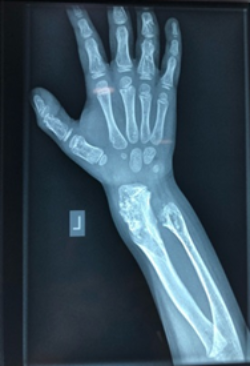

Olier’s disease

The images show a case of Olier’s disease which had a short and deformed forearm. He underwent surgical intervention by Dr. Zenios with the use of external osteosynthesis.

Pre-operative